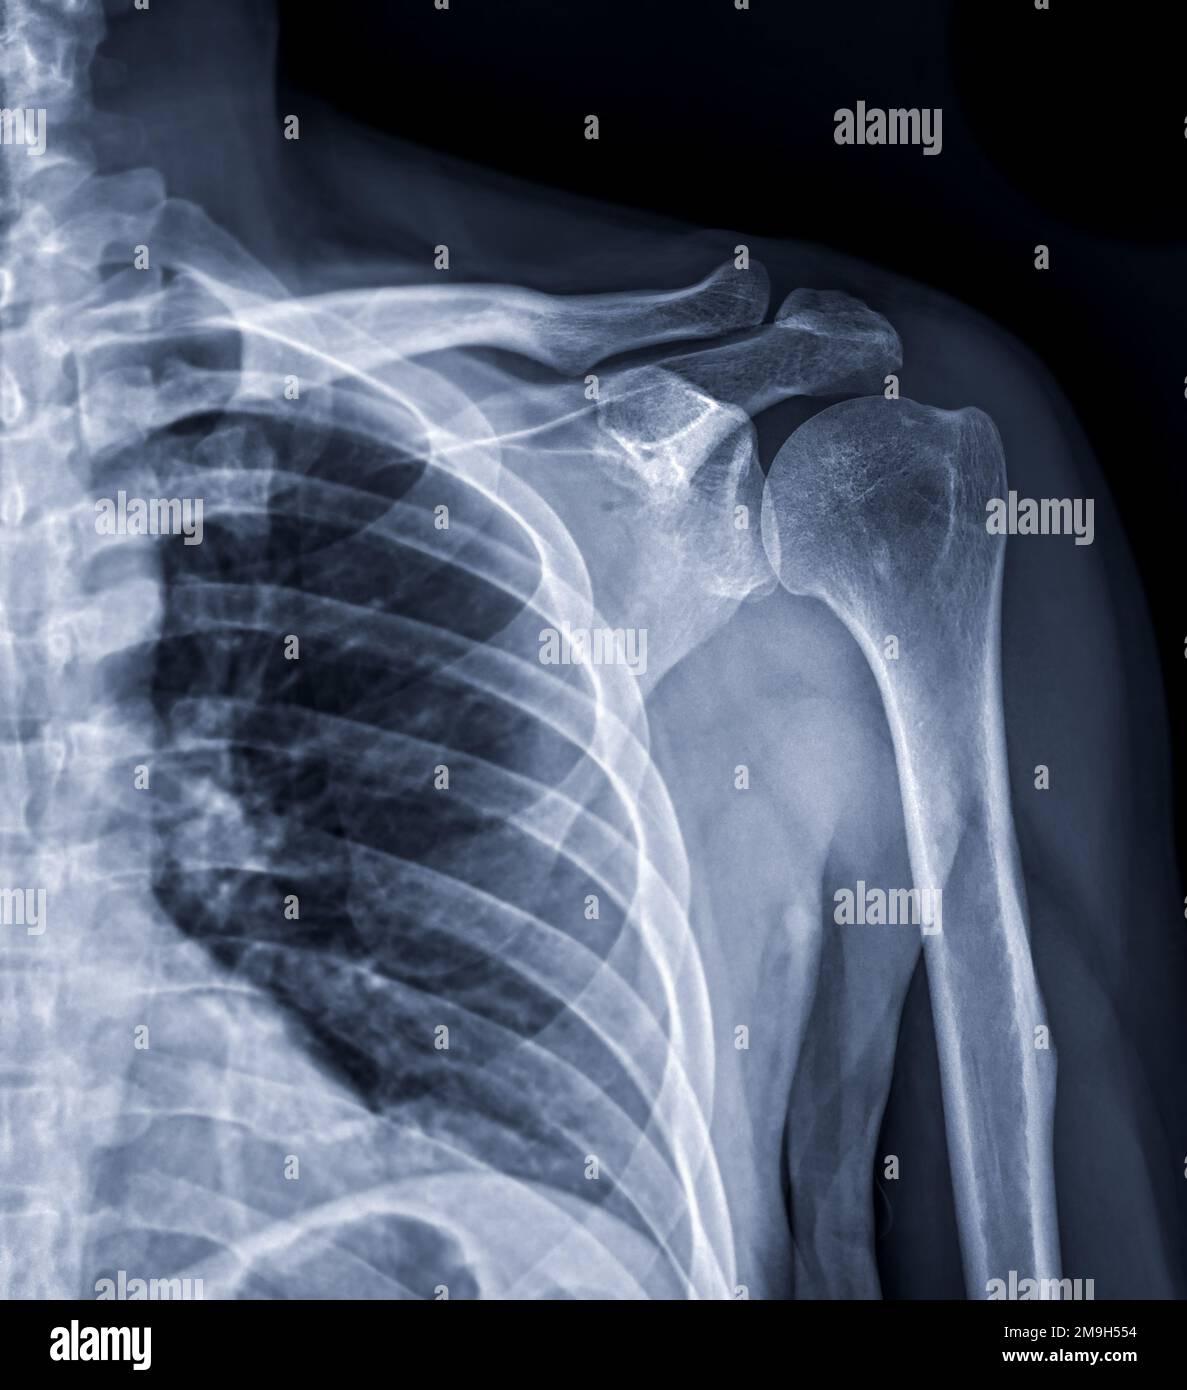

Lateral X Ray Dislocation Of Shoulder . This view is a pertinent. Be comfortable with multiple reduction techniques. Shoulder dislocation is a term often used loosely to indicate dislocation of the head of the humerus from the glenoid of the scapula. Shoulder dislocation (correctly termed a glenohumeral joint dislocation) involves separation of the humerus from the glenoid of. Capturing images from different angles. Carefully review radiographs for posterior dislocations as they may appear “normal” on first glance; The lateral scapula shoulder or y view is part of the standard shoulder series. Orthogonal to the ap shoulder (note: The humeral head will lie medial and inferior to the glenoid. As is an axillary view); The shoulder can dislocate posteriorly, but.

Lateral X Ray Dislocation Of Shoulder The lateral scapula shoulder or y view is part of the standard shoulder series. Shoulder dislocation (correctly termed a glenohumeral joint dislocation) involves separation of the humerus from the glenoid of. Shoulder dislocation is a term often used loosely to indicate dislocation of the head of the humerus from the glenoid of the scapula. Carefully review radiographs for posterior dislocations as they may appear “normal” on first glance; As is an axillary view); The shoulder can dislocate posteriorly, but. The lateral scapula shoulder or y view is part of the standard shoulder series. Be comfortable with multiple reduction techniques. Orthogonal to the ap shoulder (note: Capturing images from different angles. The humeral head will lie medial and inferior to the glenoid. This view is a pertinent.